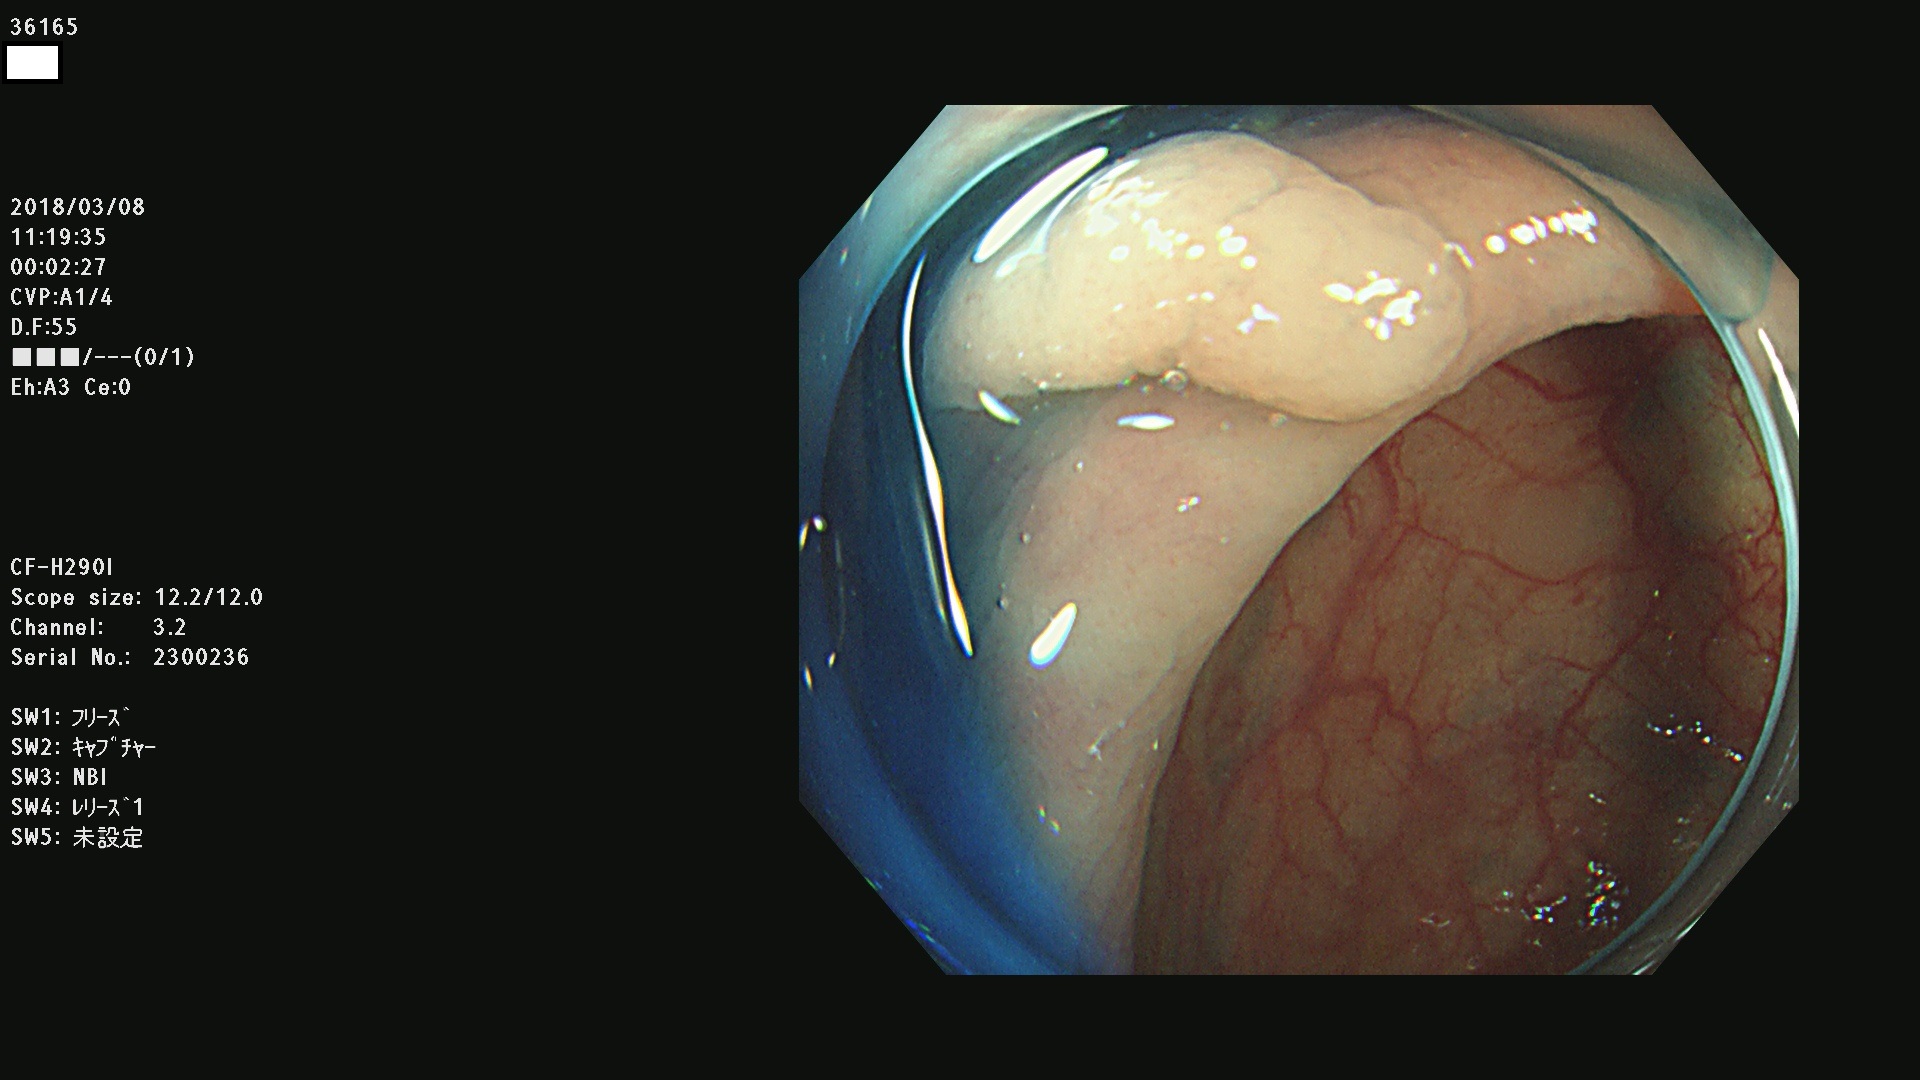

腺腫発見率57 % (カルテ番号 36100〜36199の100名の方の検査結果で集計)大腸癌検診最新情報

以下のカルテ番号の方に腺腫(Adenoma,Group3〜5)が見つかりました(集計法)

36100 36101 36102 36103 36104 36105 36107 36108 36110 36111 36114 36115 36117 36119 36120 36122 36125 36127 36129(SSA/Pのみ) 36133 36135 36137 36138 36139 36143 36144 36146 36147 36152 36153 36154 36155 36157(SSA/Pのみ) 36158 36162 36163 36165 36167 36169 36170 36173 36174 36176 36177 36178 36179 36180 36183 36185 36187 36189 36190(SSA/Pのみ) 36191 36193 36195(SSA/Pのみ) 36197(SSA/Pのみ) 36199(SSA/Pのみ)

発見困難で危険性の高い平坦型病変(上記100名より抽出) ![]()